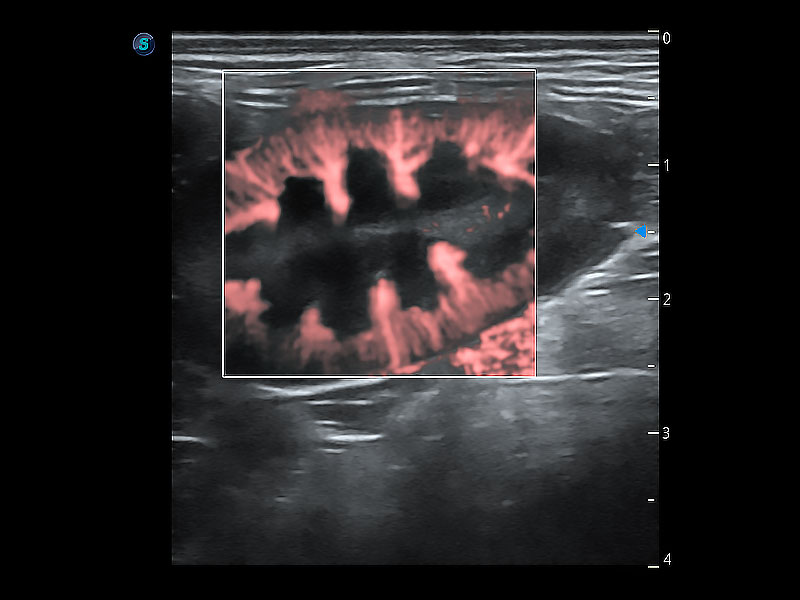

为精细结构及组织边缘提供高清晰度的图像和更大的成像视野。帮助减轻医生的用眼疲劳,快速精准获得测量的数据。